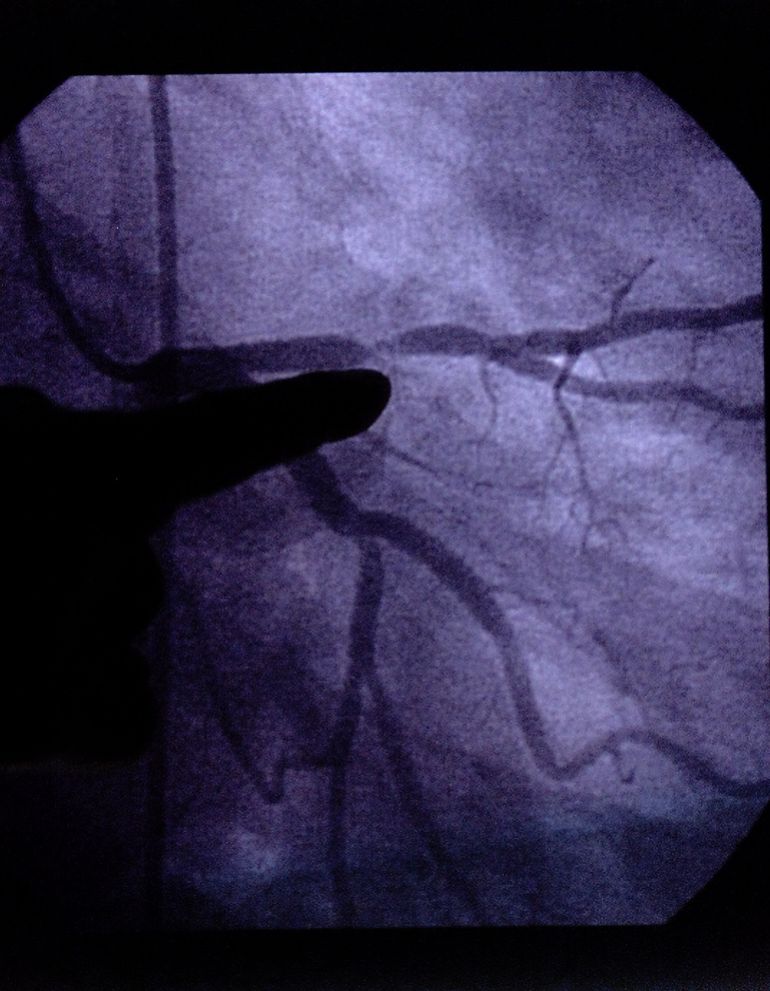

وتعيد عملية “مجازة الشريان التاجي” توجيه مسار الدم حول انسداد في الشريان الذي يحمله إلى القلب، وفي هذه العملية الجديدة، تم إدخال الأدوات الجراحية وتمريرها من خلال وعاء دموي في ساق المريض، وفقا لتقرير نُشر في مجلة “سيركيوليشن كارديوفاسكيولار إنترفينشنز” (Circulation: Cardiovascular Interventions).

وبعد ستة أشهر من الإجراء، لم تظهر على المريض أي علامات لانسداد الشريان التاجي، مما يعني أن الطريقة الجديدة كانت ناجحة.